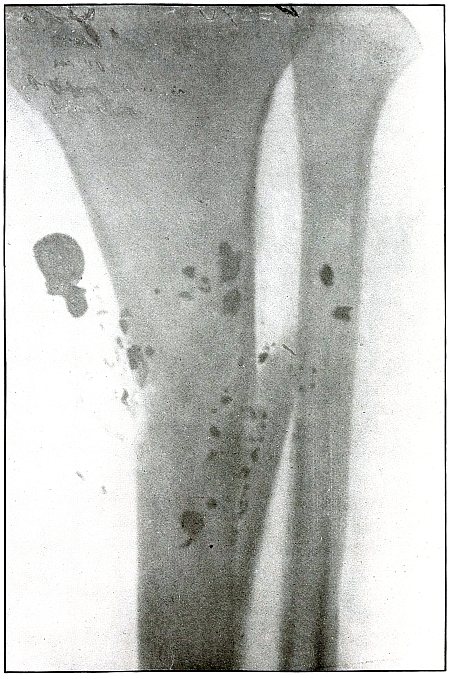

Plate 63.

_

Rifle—Plate 63.

LOWER EXTREMITY.

Gunshot Wound of the Middle of the Tibia,

with Few Large Fragments.

The course of the bullet was transverse from without inward.

The direct impact of the bullet, in high velocity of short range, has produced the typical “X” fracture due to the radiating lines of force.

The wound was infected, as is shown by the drainage tubes in the wound.

The emergency treatment in such cases is simple antiseptic dressing and temporary splint immobilization.

The subsequent treatment is the management of the infection.

The results in such cases are favorable. [Pg 138]